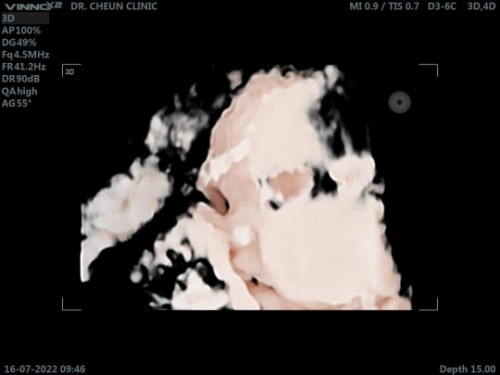

นน.3100 กรัม 36+6วีค มากรึน้อยไปค่ะ .แม่ๆทีมสิงหาน้ำหนักกันเท่าไหร่กันมั้งค่ะต้องบำรุงอีกเยอะมั้ย #ขอบคุณล่วงหน้านะคะ